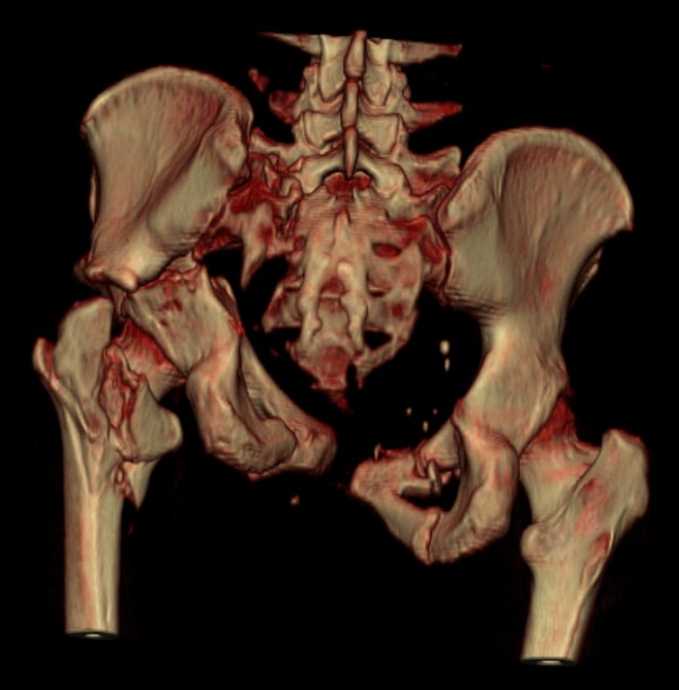

Больная 43 года (промышленный альпинист), 28.07.08 в результате падения с 5 этажа получила политравму:

Перелом свода и основания черепа. Вертикально-нестабильное повреждение таза, осложнённое разрывом мочевого пузыря. Чрезвертельный перелом левого бедра. Перелом правой таранной кости, переломовывих правой кубовидной кости. Тупая травма живота, разрыв печени, ушиб почек. Забрюшинная гематома. В день травмы - лапаротомия, ушивание ран печени. Разрыв мочевого пузыря не диагностирован. Течение болезни осложнилось развитием мочевого затёка и обширной пред- и забрюшинной флегмоны, сформировался свищ мочевого пузыря. 19.8.2008 вскрытие, дренировние флегмоны, ревизия мочевого пузыря, обтурация мочевого свища (свищ закрылся в октябре), 1.10.2008 некрэктомия, пластика по Шеде-Лидскому правой кубовидной кости. По результатам КТ диагностирован рак правой почки (диагностическая находка), 8.10.2008 нефрэктомия справа.

Переломы велись консервативно.

Имеется вертикальное смещение левой половины таза с выраженным отведением крыла (клинически подвижности нет), несросшийся низкий двухколонный перелом левой вертлужной впадины с потерей конгруэнтности, укорочение около5 см, застарелый разрыв лонного сочленения, неправильно сросшиеся переломы обеих ветвей правой лонной кости с укорочением, патологическая подвижность лоно-седалищного фрагмента слева. Правая нижняя конечность неопорна, несмотря на то, что лежа прямую ногу поднимает, ходит на левой ноге (ортопедическая обувь) с костылями, справа тазобедренный ортез. Седалищные нервы работают.Урологи отпустили больную на 6 мес.

Мучаемся мыслями - как все это заставить ходить.Возможно ли первичное протезирование если просто синтезировать лонное сочленение с цементом и ванкомицином?

Если делать большую реконструкцию, то с чего начать? Изрубить крыло и заполнить дефекты? Перерубить боковую массу и попытаться развернуть крыло обратно?